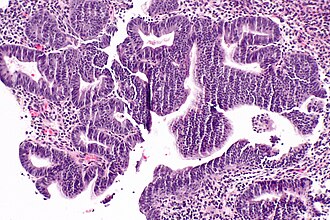

Template:Px Complex endometrial hyperplasia. H&E stain. | |

| LM | increase in size & number of glands + irregular shape, nuclear pseudostratification, nuclear enlargement, mitoses common, +/-nuclear atypia (round nuclei ~ 2-3x the size of a lymphocyte, grey/translucent chromatin, nucleoli) |

- Increase in size & number of glands + irregular shape - key feature.

- Cell stratification.

- Nuclear enlargement.

- Mitoses common.

- +/-Nuclear atypia:

- Round nuclei ~ 2-3x the size of a lymphocyte.

- Grey/translucent chromatin.

- Nucleoli.